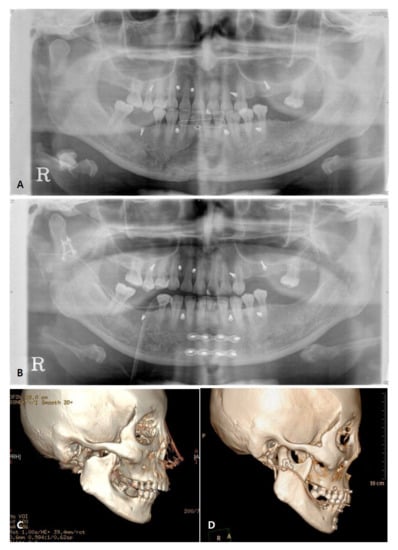

3.3. Radiographic Evaluation